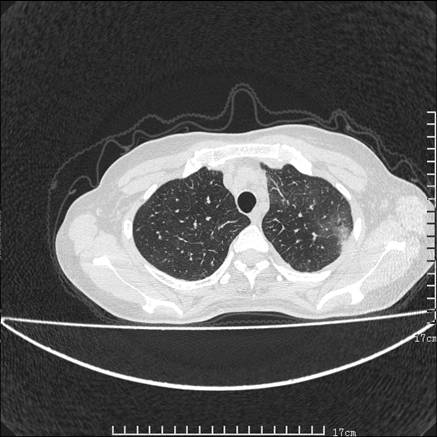

女,46岁,患胃溃疡多年,溃疡大小约1.0cm左右,后于5年前手术,病理为胃癌。主诉:半月前感冒后胸闷,气短,有咳嗽,无明显咳痰,无发热。偶有腰背部不适。

以下为高分辨扫描图像

双肺散在的 磨玻璃样及片状渗出性病灶,界限模糊。考虑:双肺感染!

双肺小叶间增厚,双肺散布粟米影和磨玻璃状影,以双肺上叶为重。结合病史考虑转移(癌性淋巴细管炎)可能性大。